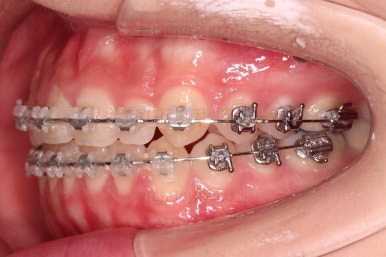

왜소치가 있어서 중앙선과 교합을 맞추는데 약간의 애로사항이 있었지만 최대한 잘 마무리를 하였습니다.

앞니 각도, 가지런한 느낌, 덧니 등 모든 점이 다 개선되었네요.

입안의 모습에서도 모든게 다 좋아졌고요.

웃는 모습과도 매우 조화롭게 치열이 가지런해졌네요.

앞니 각도가 개선되면서 웃을 때 보이는 치열도 가득차 보이고 환해보이고요.